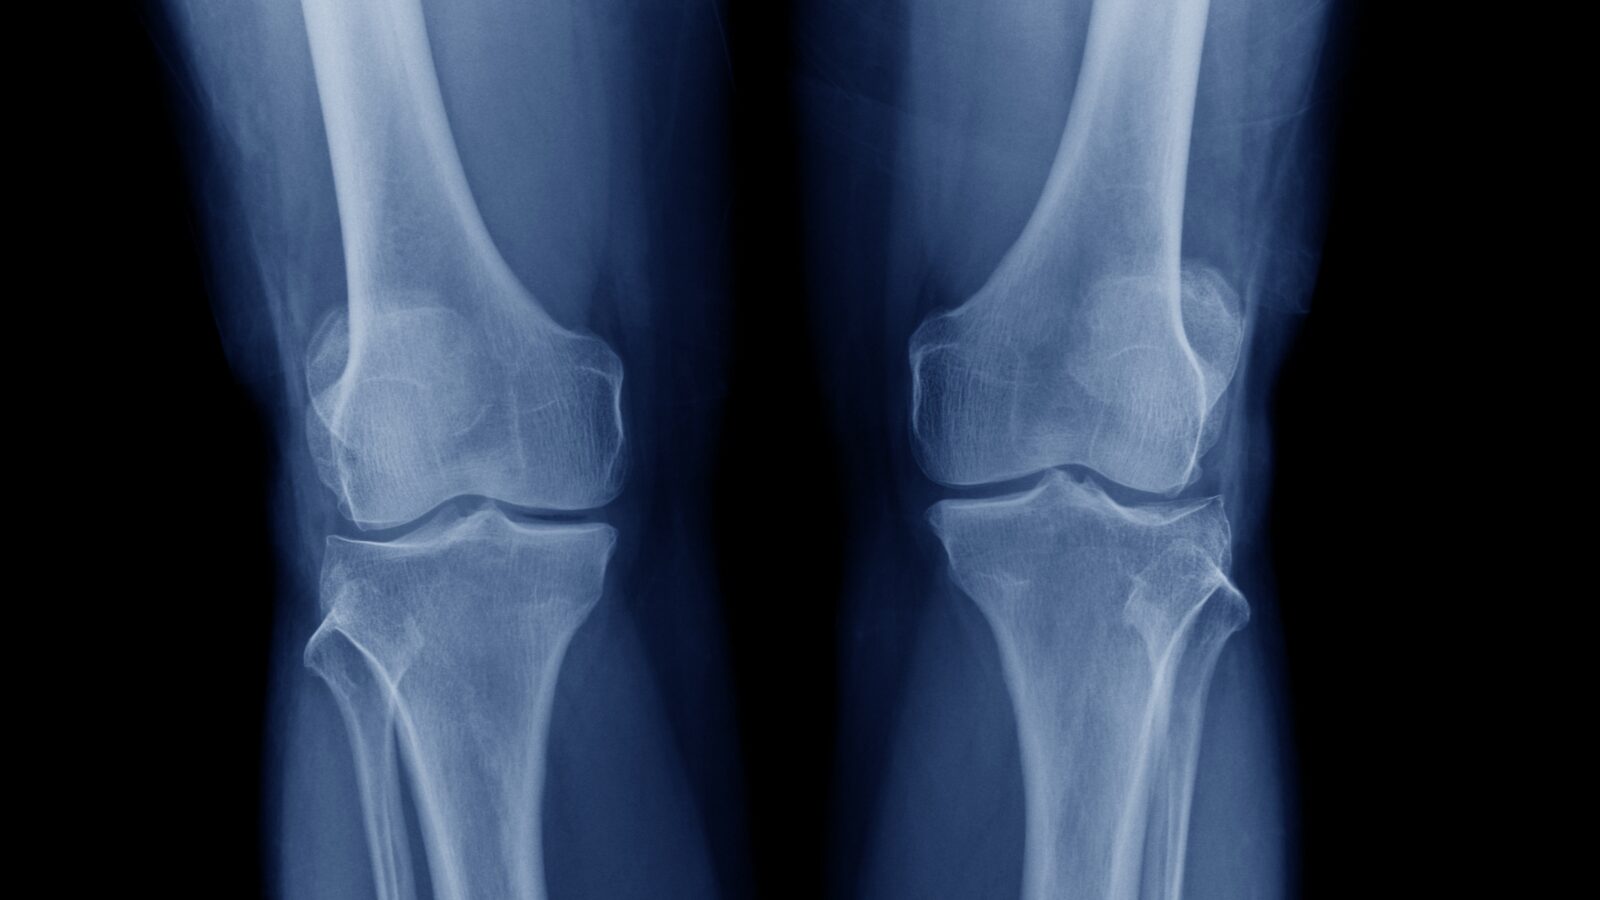

画像検査で異常が見つからないのは、実は身体の使い方が原因だからなんです。レントゲンやMRIでは、骨や軟骨の状態はわかりますが、「どのように身体を動かしているか」まではわかりません。

ヘルニアがあっても、軟骨が磨り減っていても、痛くない人は全く痛くないですし、きれいな脊柱であっても、軟骨もしっかり写っていても痛い人は痛いんです。